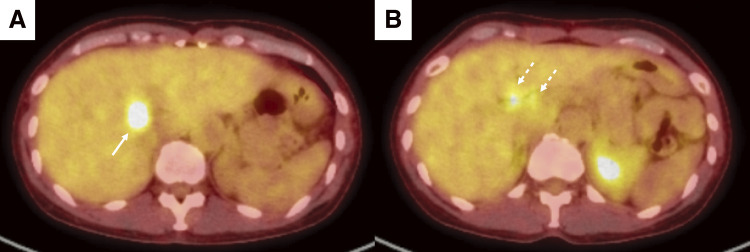

Case presentation: A 52-year-old woman was referred to our hospital and was subsequently diagnosed with bilateral breast cancer. Computed tomography (CT) and magnetic resonance imaging incidentally detected a liver tumor in the hilar region and lymph node enlargement in the hepatoduodenal ligament. A 19 mm tumor was observed in the area surrounded by the right and left branches of the portal vein and an abnormal portal branch of segment 7. Positron emission tomography-CT showed fluorodeoxyglucose uptake in the liver tumor, hepatoduodenal ligament lymph nodes, and bilateral breasts. A tumor biopsy showed a papillary tumor, and ICC was suspected. As ICC with LNM has a poor prognosis, neoadjuvant chemotherapy was planned. Genetic testing using a blood sample revealed a BRCA2 mutation, indicating the patient would benefit from chemotherapy, particularly cisplatin. The patient received a chemotherapy regimen comprised of gemcitabine, cisplatin, and S-1 (GCS), and after 7 courses, her carbohydrate antigen 19-9 level decreased from 2433 to 15 U/mL. CT showed that the tumor had shrunk and the LNMs were indistinct. The patient was referred to our department for curative surgery, which included a left hepatectomy, caudate lobectomy, hepatoduodenal ligament lymph node dissection, bile duct resection, and choledocojejunostomy. The postoperative course was generally uneventful, and the patient was discharged on postoperative day 18. Pathological examination of the resected specimen revealed an absence of malignant cells. At 24 months postoperative, there was no evidence of recurrence.